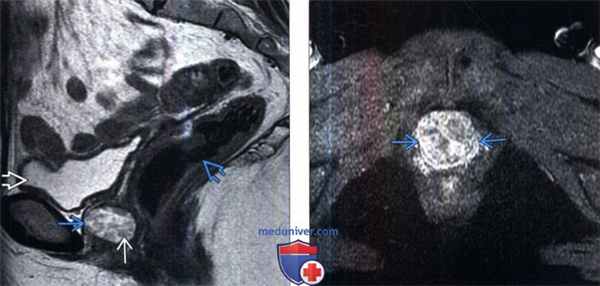

(Слева) Микционная цистоуретрография в переднезадней проекции: у этого же пациента определяется кольцевидное заполнение контрастным веществом дивертикула уретры. Устье ди -вертикула находится на заднебоковой стенке справа. Контрастное вещество в мочевом пузыре.

(Справа) МРТ, Т2-ВИ в последовательности одиночного быстрого спин-эхо, аксиальный срез: у этого же пациента обнаружен сигнал высокой интенсивности от дивертикула , который окружает уретру . Определяется тонкая частичная перегородка вдоль правой заднебоковой стенки дивертикула.